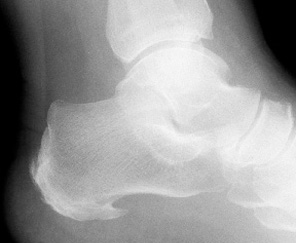

Na początek krótkie przybliżenie anatomii [ryc.1]. Na tylnej części kości piętowej przymocowuje się ścięgno mięśnia trójgłowego łydki – ścięgno Achillesa. Na guzowatości kości piętowej natomiast ma swój początek rozcięgno podeszwowe, które rozdziela się na 5 pasm, biegnących aż do podstawy paliczków bliższych kolejnych palców stopy. [1]

Rozcięgno podeszwowe jest kluczową strukturą podczas walki z ostrogą piętową. Stanowi ono bowiem podporę dla łuku podłużnego stopy, dzięki któremu siła nacisku podczas chodu czy biegu na podłoże jest równomiernie rozkładana i amortyzowana.

- https://upload.wikimedia.org/wikipedia/commons/3/33/Calc_spur.jpg